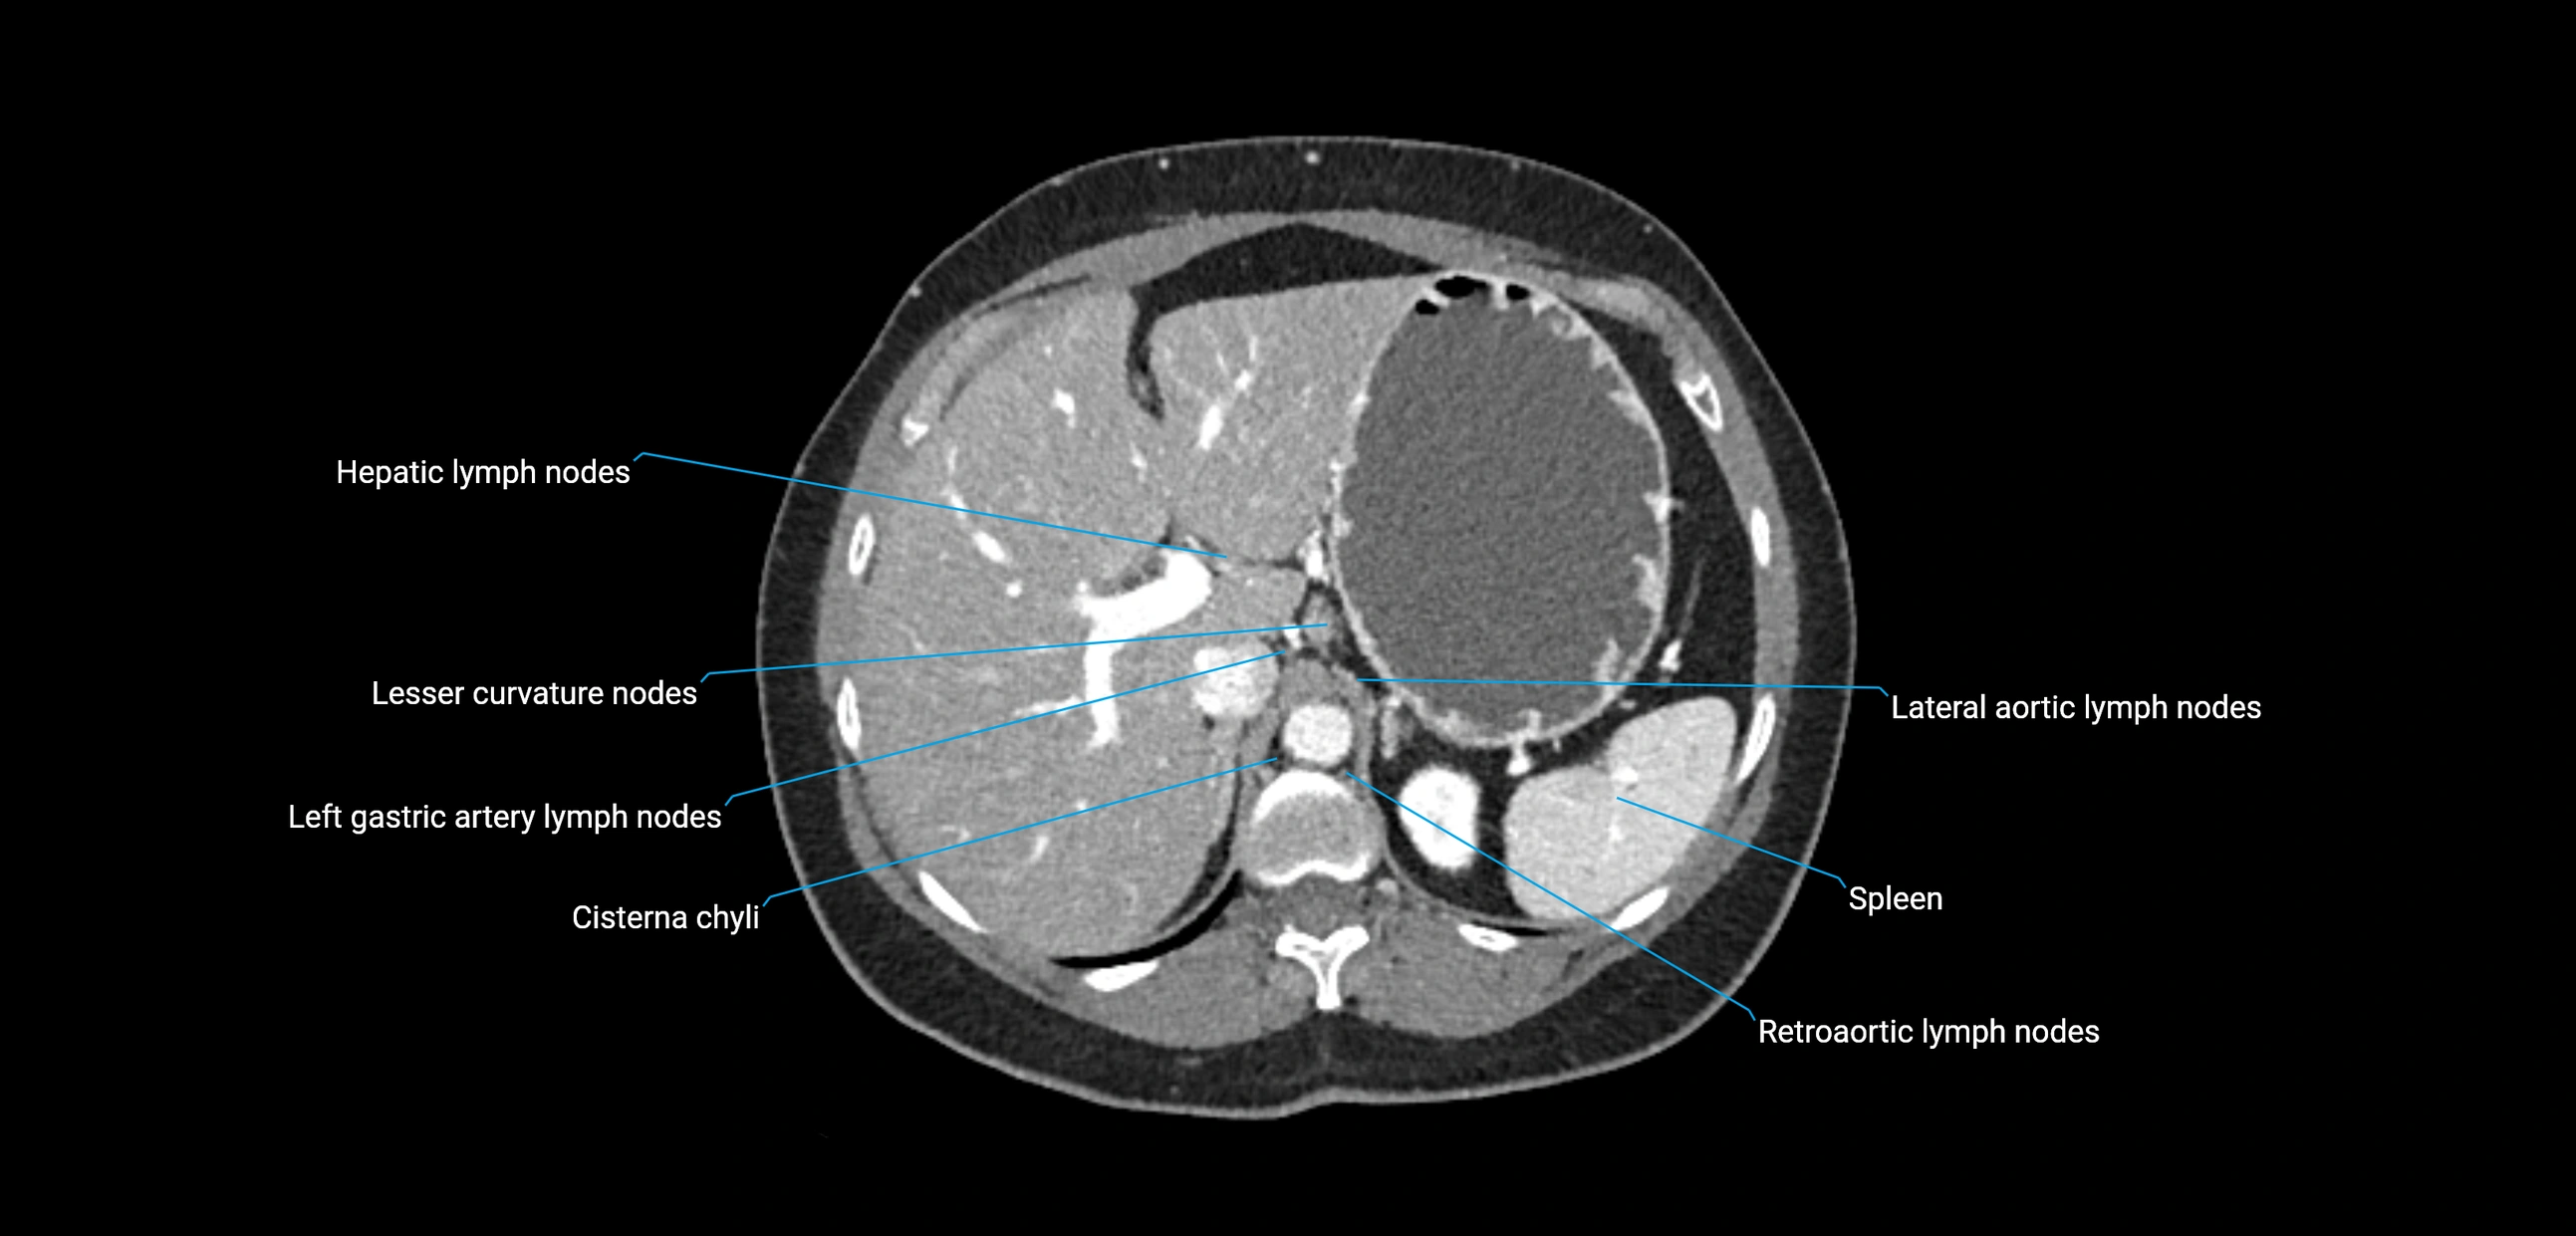

CT Appearance

CT Pre-Contrast:

• Nodes appear as soft-tissue density nodules adjacent to the aorta and IVC

• Calcification may be seen in chronic infections (e.g., tuberculosis)

CT Post-Contrast:

• Normal nodes enhance homogeneously

• Malignant nodes may show heterogeneous enhancement, central necrosis, or conglomerate formation

• Size >1 cm short axis is suspicious, though morphology and distribution are equally important

CT Venography (CTV):

• Demonstrates nodal encasement or compression of adjacent vessels (aorta, IVC, renal veins)

• Useful in staging testicular and ovarian malignancies

• Provides 3D reconstructions for retroperitoneal lymph node dissection planning

CT image

image